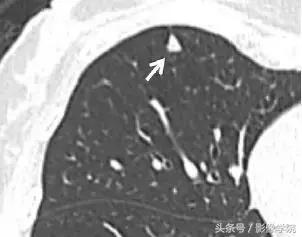

5、肺内淋巴结

图 5 CT 图像,显示一个三角形实性胸膜下结节(箭头),且呈线状延伸至胸膜表面,为典型的肺内淋巴结表现,不建议 CT 随访。